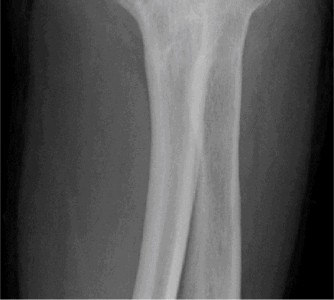

Treat a patient with infected total shoulder arthroplasty? CASE 21 A 70-year-old, right-hand-dominant female presents to clinic complaining of 4 years of gradually worsening chronic right shoulder pain and stiffness. She says the pain is worse at night and with any range of motion, denies a history of trauma, pain in other extremities, or numbness or tingling of the right upper extremity. She notes that her mother suffered from rheumatoid arthritis that affected her shoulder. Physical examination reveals decreased muscle bulk over the right supra- and infraspinatus fossae compared to the contralateral side, limited active and passive ROM, marked weakness with external rotation, and 4+/5 strength with shoulder abduction. X-rays of the right shoulder are shown in Figures 2–58 and 2–59.

The correct answer is (C). Rotator cuff tear arthropathy consists of a combination of rotator cuff insufficiency, glenohumeral joint degenerative changes, and superior humeral head migration. It is more common in women and also more often found on the dominant side. The patient’s clinical examination with weakened external

rotation and muscle atrophy signaling incompetent supra- and infraspinatus muscles point to rotator cuff insufficiency, and her plain films reveal narrowed glenohumeral joint space as well as superior migration of the humeral head. Choice D is incorrect because, while radiographs would show narrowing of the glenohumeral joint space, they would also likely show numerous osteophytes and posterior wear of the glenoid. Choice B is incorrect because, while adhesive capsulitis does present as decreased active and passive range of motion, the patient’s constellation of symptoms pointing towards rotator cuff insufficiency along with the radiographs make cuff tear arthropathy the more likely choice. Finally, Choice A is incorrect because even though she has a positive family history of rheumatoid arthritis, it is less likely to present only in a single joint. Also, rheumatoid arthritis on radiography appears more as an erosive process without the characteristic superior migration of the humeral head.

The correct answer is (A). Superior migration of the humeral head would be most indicative of chronic rotator cuff insufficiency associated with cuff tear arthropathy, as it is a direct result of the inability of the rotator cuff tendons to help maintain the humerus in its normal position. Acetabularization of the undersurface of the acromion is commonly associated with superior migration of the humeral head found in rotator cuff tear arthropathy, and can be assessed using the Hamada classification, which is based on measurements of the acromiohumeral interval on radiography (Table 2–8). Choices B and C are incorrect because, while narrowed glenohumeral joint space and subchondral sclerosis are associated with rotator cuff arthropathy on radiographs, they indicate degenerative joint changes rather than chronic rotator cuff insufficiency. Choice D is incorrect because it is not a specific sign of rotator cuff arthropathy.